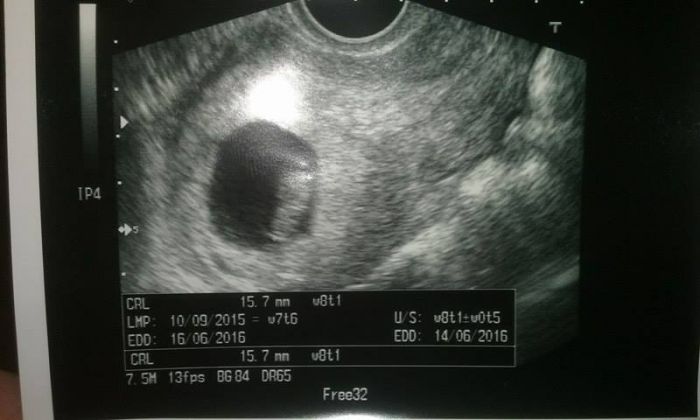

tak znovu a už oficiálně ;) dnes ráno hnědý výtok a úprk na gyndu... takže prcek už má 1,6 cm, přesně odpovídá ms (7+6) a vše v pořádku. spíš si za to můžu sama, jak jsem se včera pořád kontrolovala a rupla nějaká cevka ;) každopádně je mi daleko lépe a o dost volněji se mi dýchá. .. za dva týdny repete

A můj malý poklad...